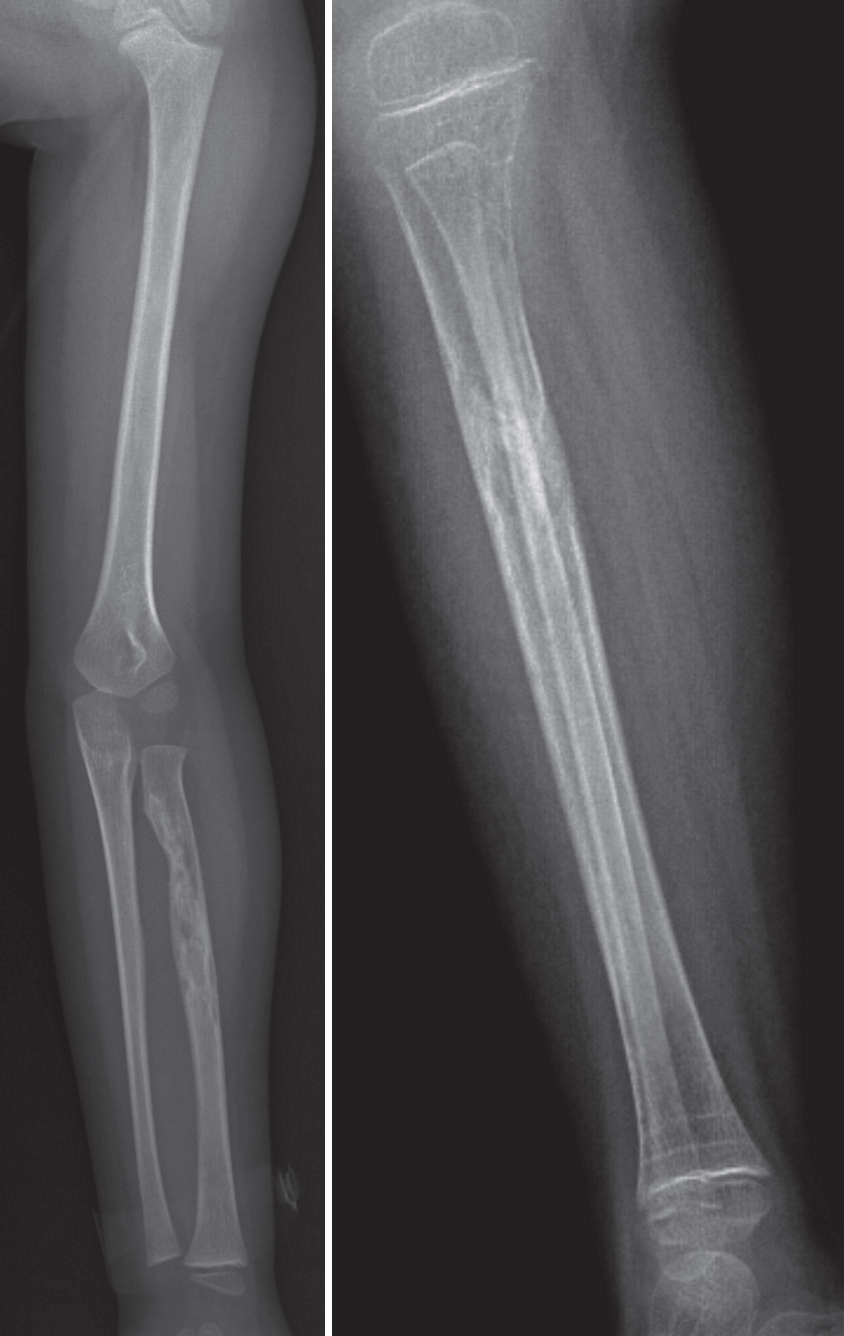

Diáfisis proximal y medial del radio izquierdo con lesión lítica, no expansiva que interrumpe el borde medial de la cortical. Cambios incipientes en el tercio proximal de tibia derecha por áreas de radiolucidez alternantes con radioopacidad.